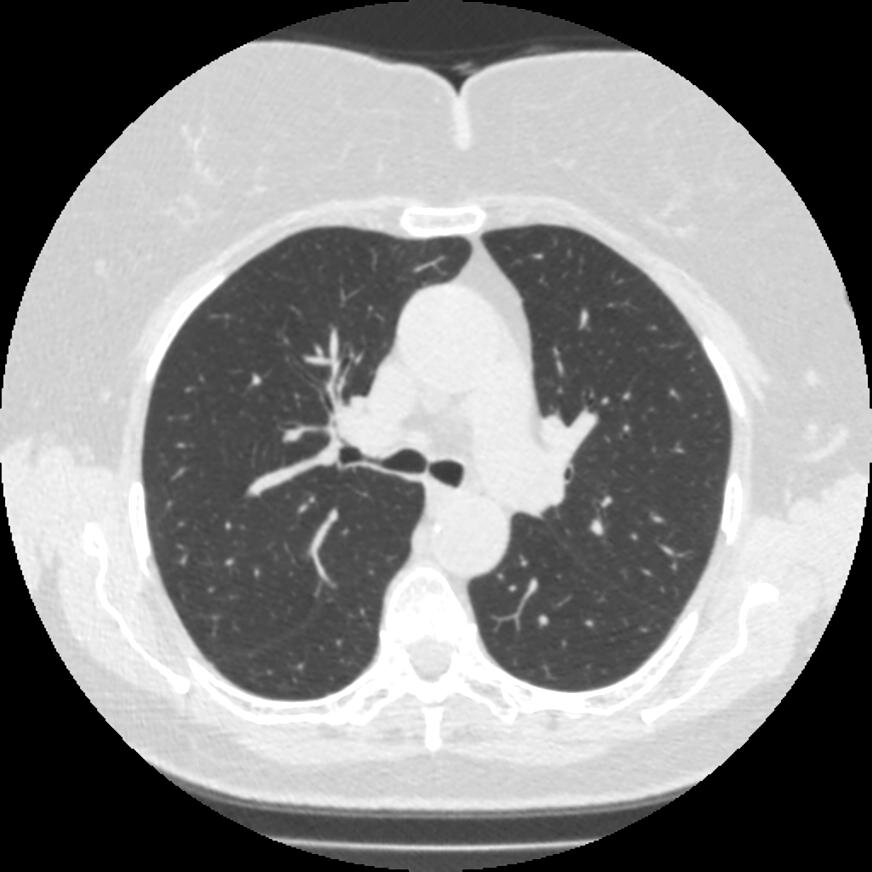

Качество картинки при НДКТ легких

На представленных картинках видно различие, первое более зернистое и снижает качество диагностики, но этого качества зачастую хватает для выявления патологии.